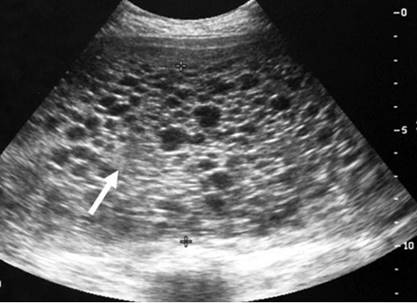

Los estudios complementarios solicitados a nivel sanguíneo demostraron varias alteraciones (tabla 2). Entre las que se destacan una disminución de los niveles séricos de hemoglobina y plaquetas; con un aumento de las cifras sanguíneas de fracción beta de gonadotropina coriónica humana (BHCG). Además, hubo otros hallazgos en las pruebas de sangre que son característicos por representar un factor de riesgo para el desarrollo de esta patología (tabla 3). A nivel ecográfico se observó quistes tecaluteínicos en ovario derecho más imágenes en tormenta de nieve (figura 1 y 2).

Figura 2: Imágenes ecolúcidas de aspecto quístico a nivel de ovario derecho.

Fuente: Historia clínica.